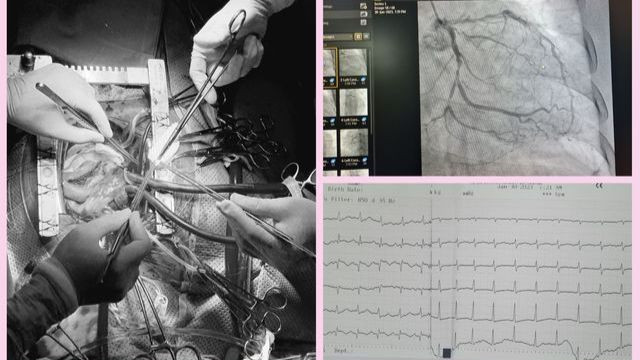

10 ngày sau đó, bệnh nhân có những cơn khó thở tăng lên rồi chuyển sang khó thở dữ dội. Sau khi bệnh nhân nhập viện, các bác sĩ nhanh chóng tiến hành siêu âm, điện tim, chụp mạch vành.

Quá trình siêu âm các bác sĩ phát hiện một lỗ thủng vách liên thất rất lớn khoảng 21,6mm, kết quả chụp mạch vành cho thấy tắc hoàn toàn động mạch vành phải (RCA), hẹp động mạch vành trái (động mạch mũ và động mạch liên thất trước).

Bệnh nhân được chẩn đoán bị nhồi máu cơ tim cấp ngày thứ 10 biến chứng thủng vách liên thất, suy tim độ 4. Nhận định tình trạng nguy kịch của bệnh nhân, các bác sĩ đã tiến hành phẫu thuật cấp cứu. Đến hiện tại sức khỏe bệnh nhân đã ổn định và được ra viện.